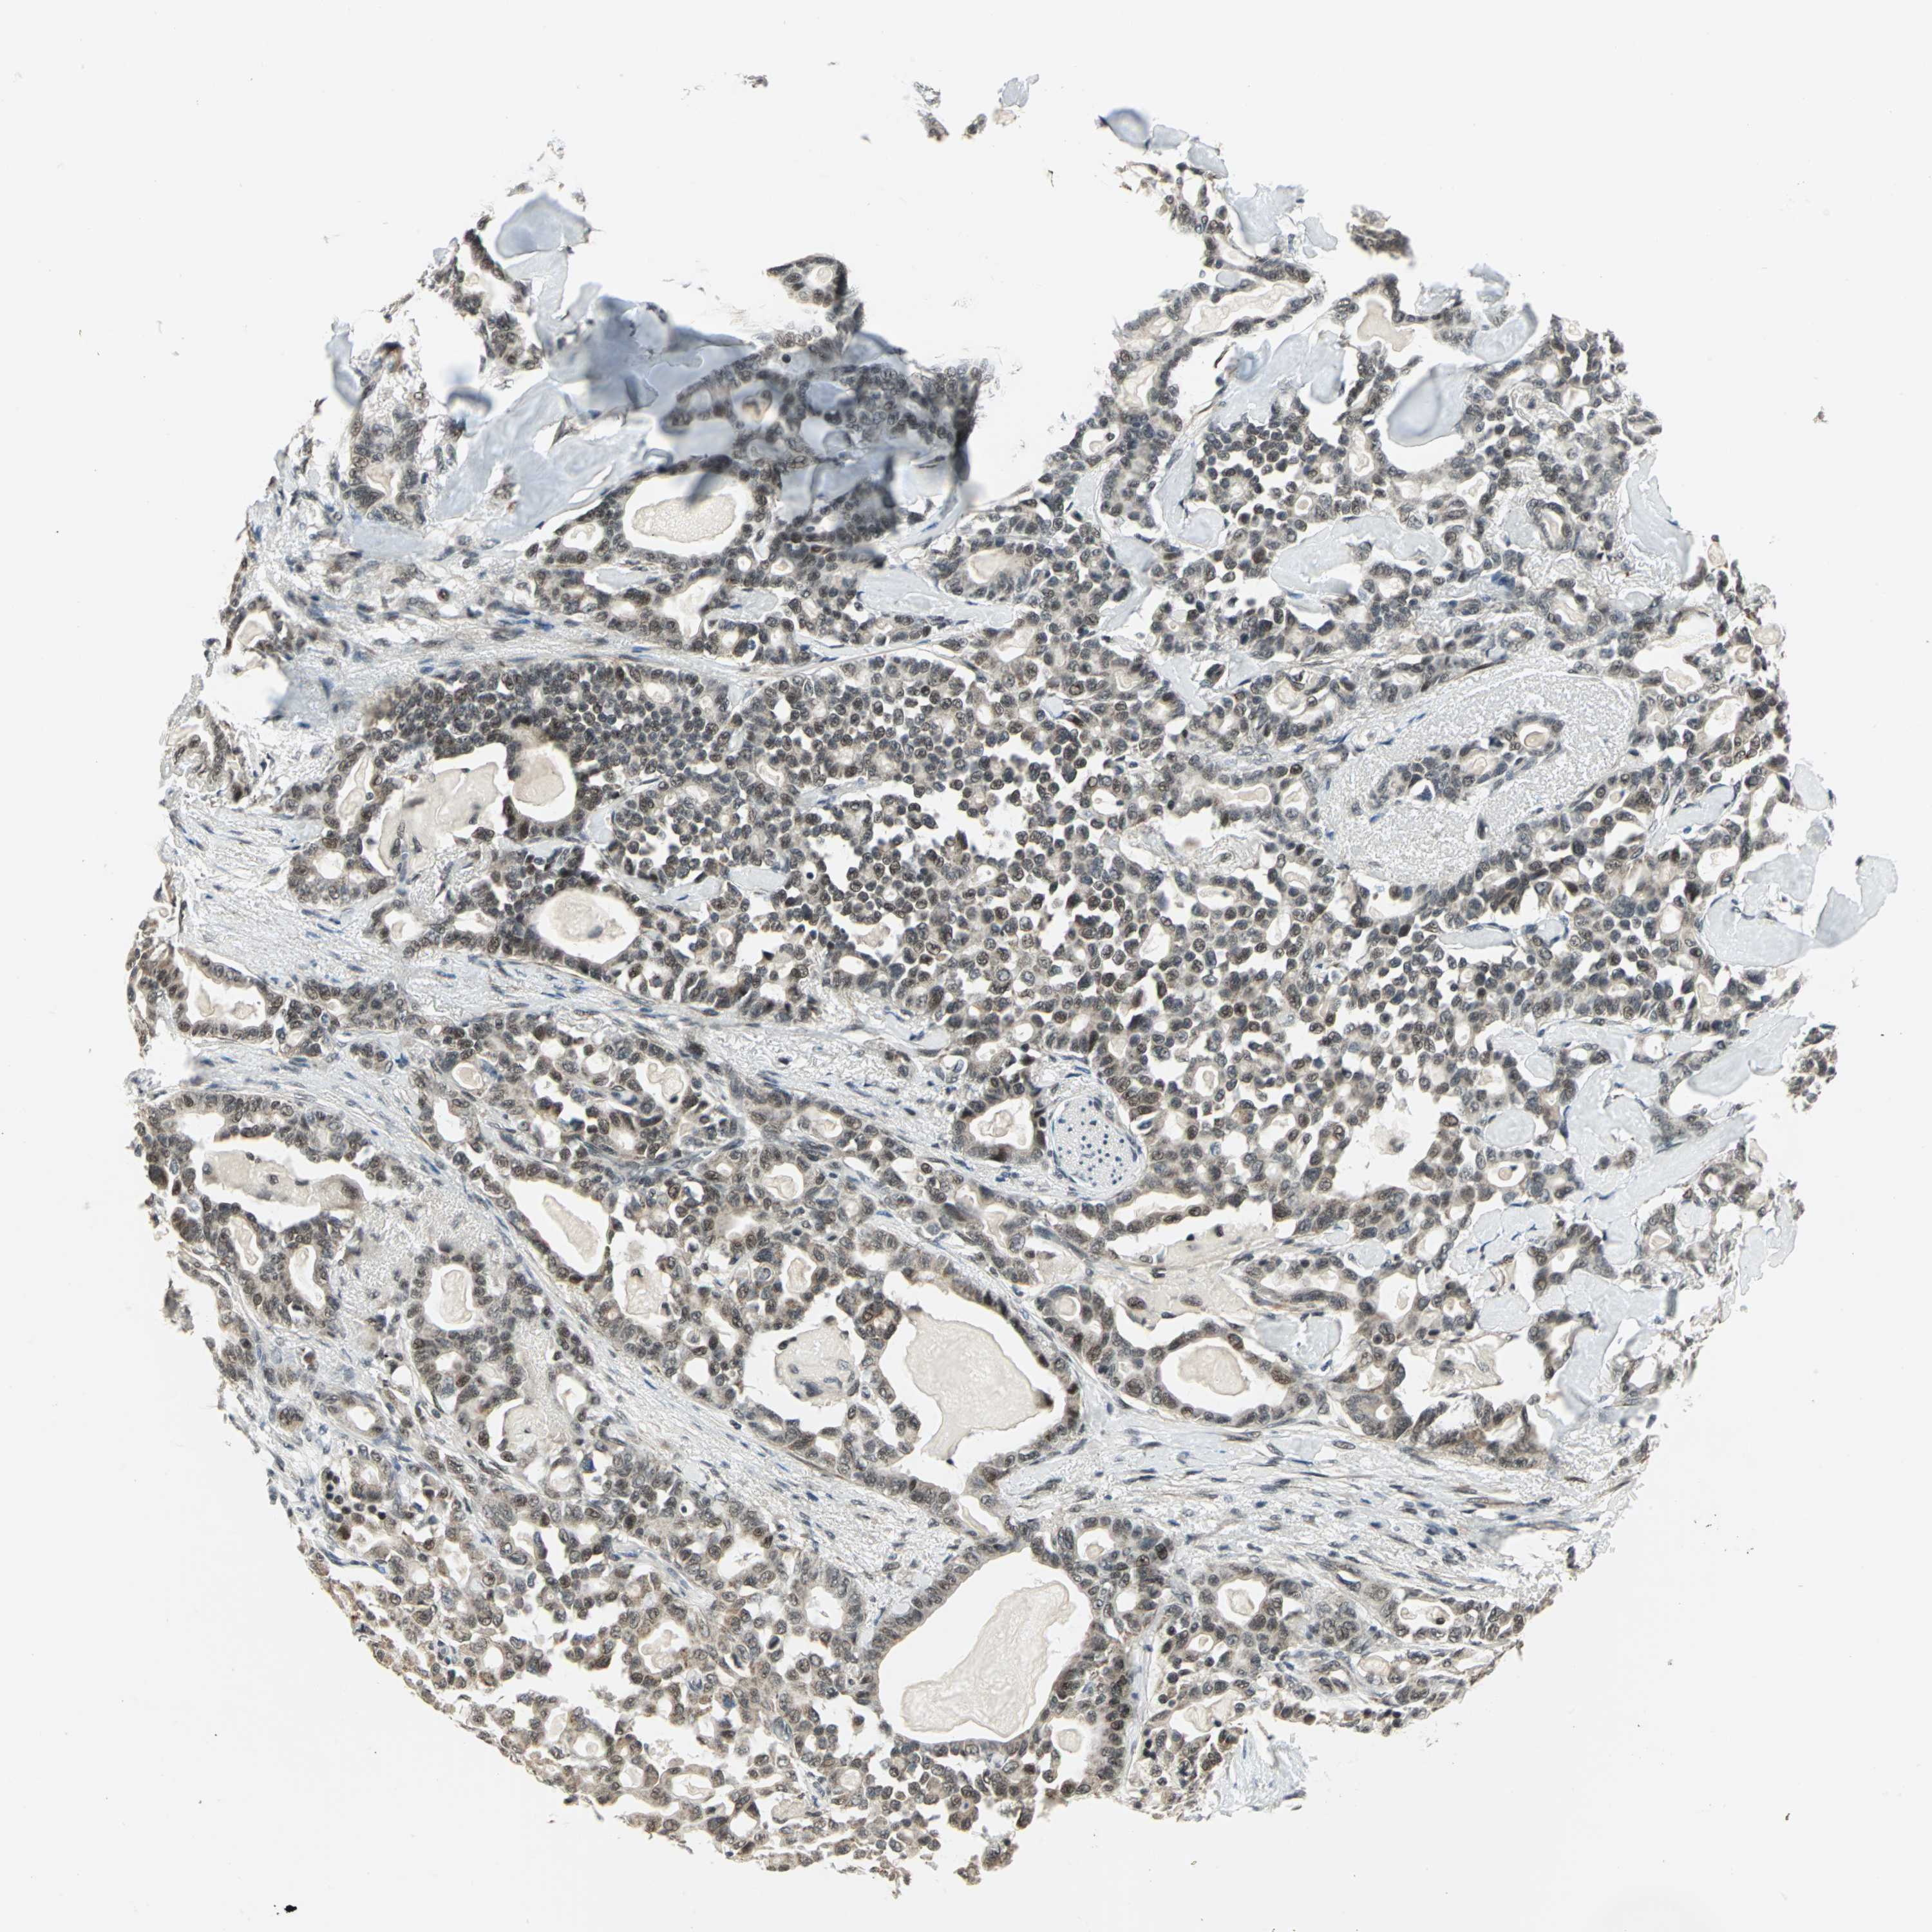

PANCREATIC CANCER - Protein expressioni

A mouse-over function shows sample information and annotation data. Click on an image to view it in a full screen mode. Samples can be filtered based on level of antibody staining by selecting one or several of the following categories: high, medium, low and not detected. The assay and annotation is described here.

Note that samples used for immunohistochemistry by the Human Protein Atlas do not correspond to samples in the TCGA dataset.

Antibody stainingi

Antibody staining in the annotated cell types in the current human tissue is reported as not detected, low, medium, or high, based on conventional immunohistochemistry profiling in selected tissues. This score is based on the combination of the staining intensity and fraction of stained cells.

Each image is clickable and will lead to virtual microscopy that enables deeper exploration of all samples and also displays staining intensity scores, fraction scores and subcellular localization as well as patient and tissue information for each sample.

Antibody HPA005544

Antibody CAB004508

Staining

High

Medium

Low

Not detected

Intensity

Strong

Moderate

Weak

Negative

Quantity

>75%

75%-25%

<25%

None

Location

Nuclear

Cytoplasmic/membranous

Cytoplasmic/membranous,nuclear

Adenocarcinoma, NOS